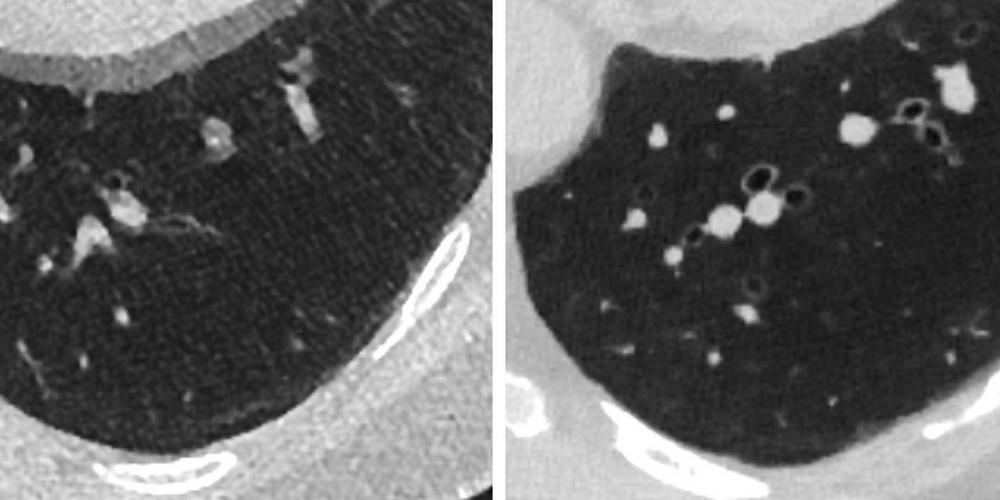

Röntgenbilder av samma lunga med två generationer av datortomografi (CT): Till vänster energiintegrerad CT som har funnits relativt oförändrad i cirka 50 år. Till höger fotonräknande CT som har använts i ett par år.

– Den nya tekniken ger mycket bättre kontrast, mindre brus och en tydligare bild av detaljerna. Man får högupplösta bilder i flera plan. Och ett stort plus är att det kan göras med lägre stråldos än tidigare typer av datortomografi.

De flesta prickar är helt harmlösa, men en liten andel kan vara tidiga tecken på lungcancer

Hon vrider, växlar perspektiv, zoomar in. Prickarna i lungan syns som små förtätningar.

– De flesta prickar är helt harmlösa, men en liten andel kan vara tidiga tecken på lungcancer. Det är en av de stora utmaningarna, att ta reda på vilka prickar som faktiskt måste följas upp, säger Åse Johnsson, professor och ämnesföreträdare för radiologi och bildbehandling vid Institutionen för kliniska vetenskaper.